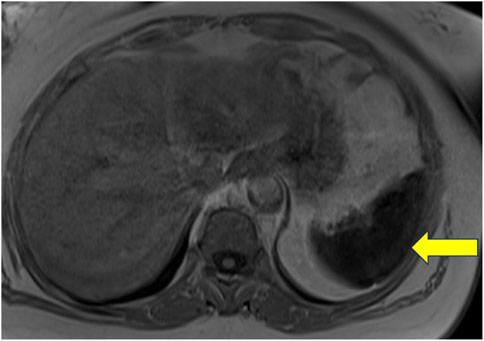

Patient 15: An adult woman of Italian ancestry presented at age 48 with thrombocytopenia and was diagnosed with GD1 due to a homozygous p.Asn409Ser GBA1 mutation. Despite responding well to ERT, she had persistently elevated ferritin and splenic iron overload on MRI (Figure 2). WES revealed a heterozygous p.His63Asp variant in the HFE gene (Hanson et al., 2001). Additionally, she was homozygous for the c.44-24G>C and synonymous p.Val221 = SNPs in the ferroportin gene, SLC40A1.

Figure 2

MRI cross-sectional image of the abdomen with a yellow arrow pointing to a darkened area on the right side, indicating a region of interest or abnormality.

Figure 2. Non-contrast MRI of the abdomen of a patient with Gaucher disease and iron overload. This image represents a T1-weighted image with a uniformly hypointense spleen, which was associated with a signal dropout on the in-phase gradient echo sequence with a longer time to echo (TE), suggestive of diffuse iron deposition.